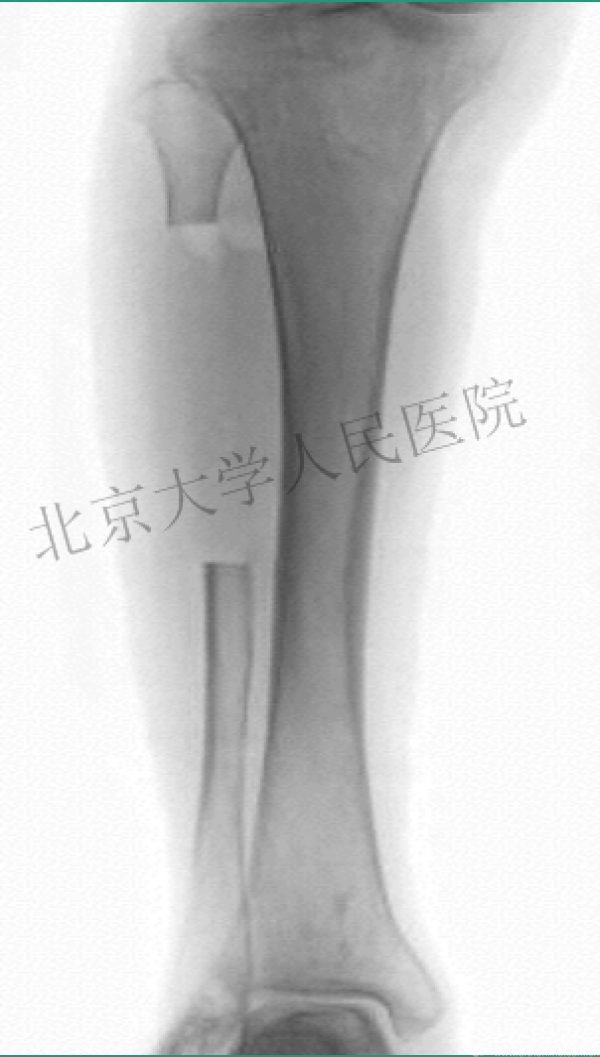

一、临床中应用钢板螺钉又有很多困惑

X射线照射后

10天后

值得吗?